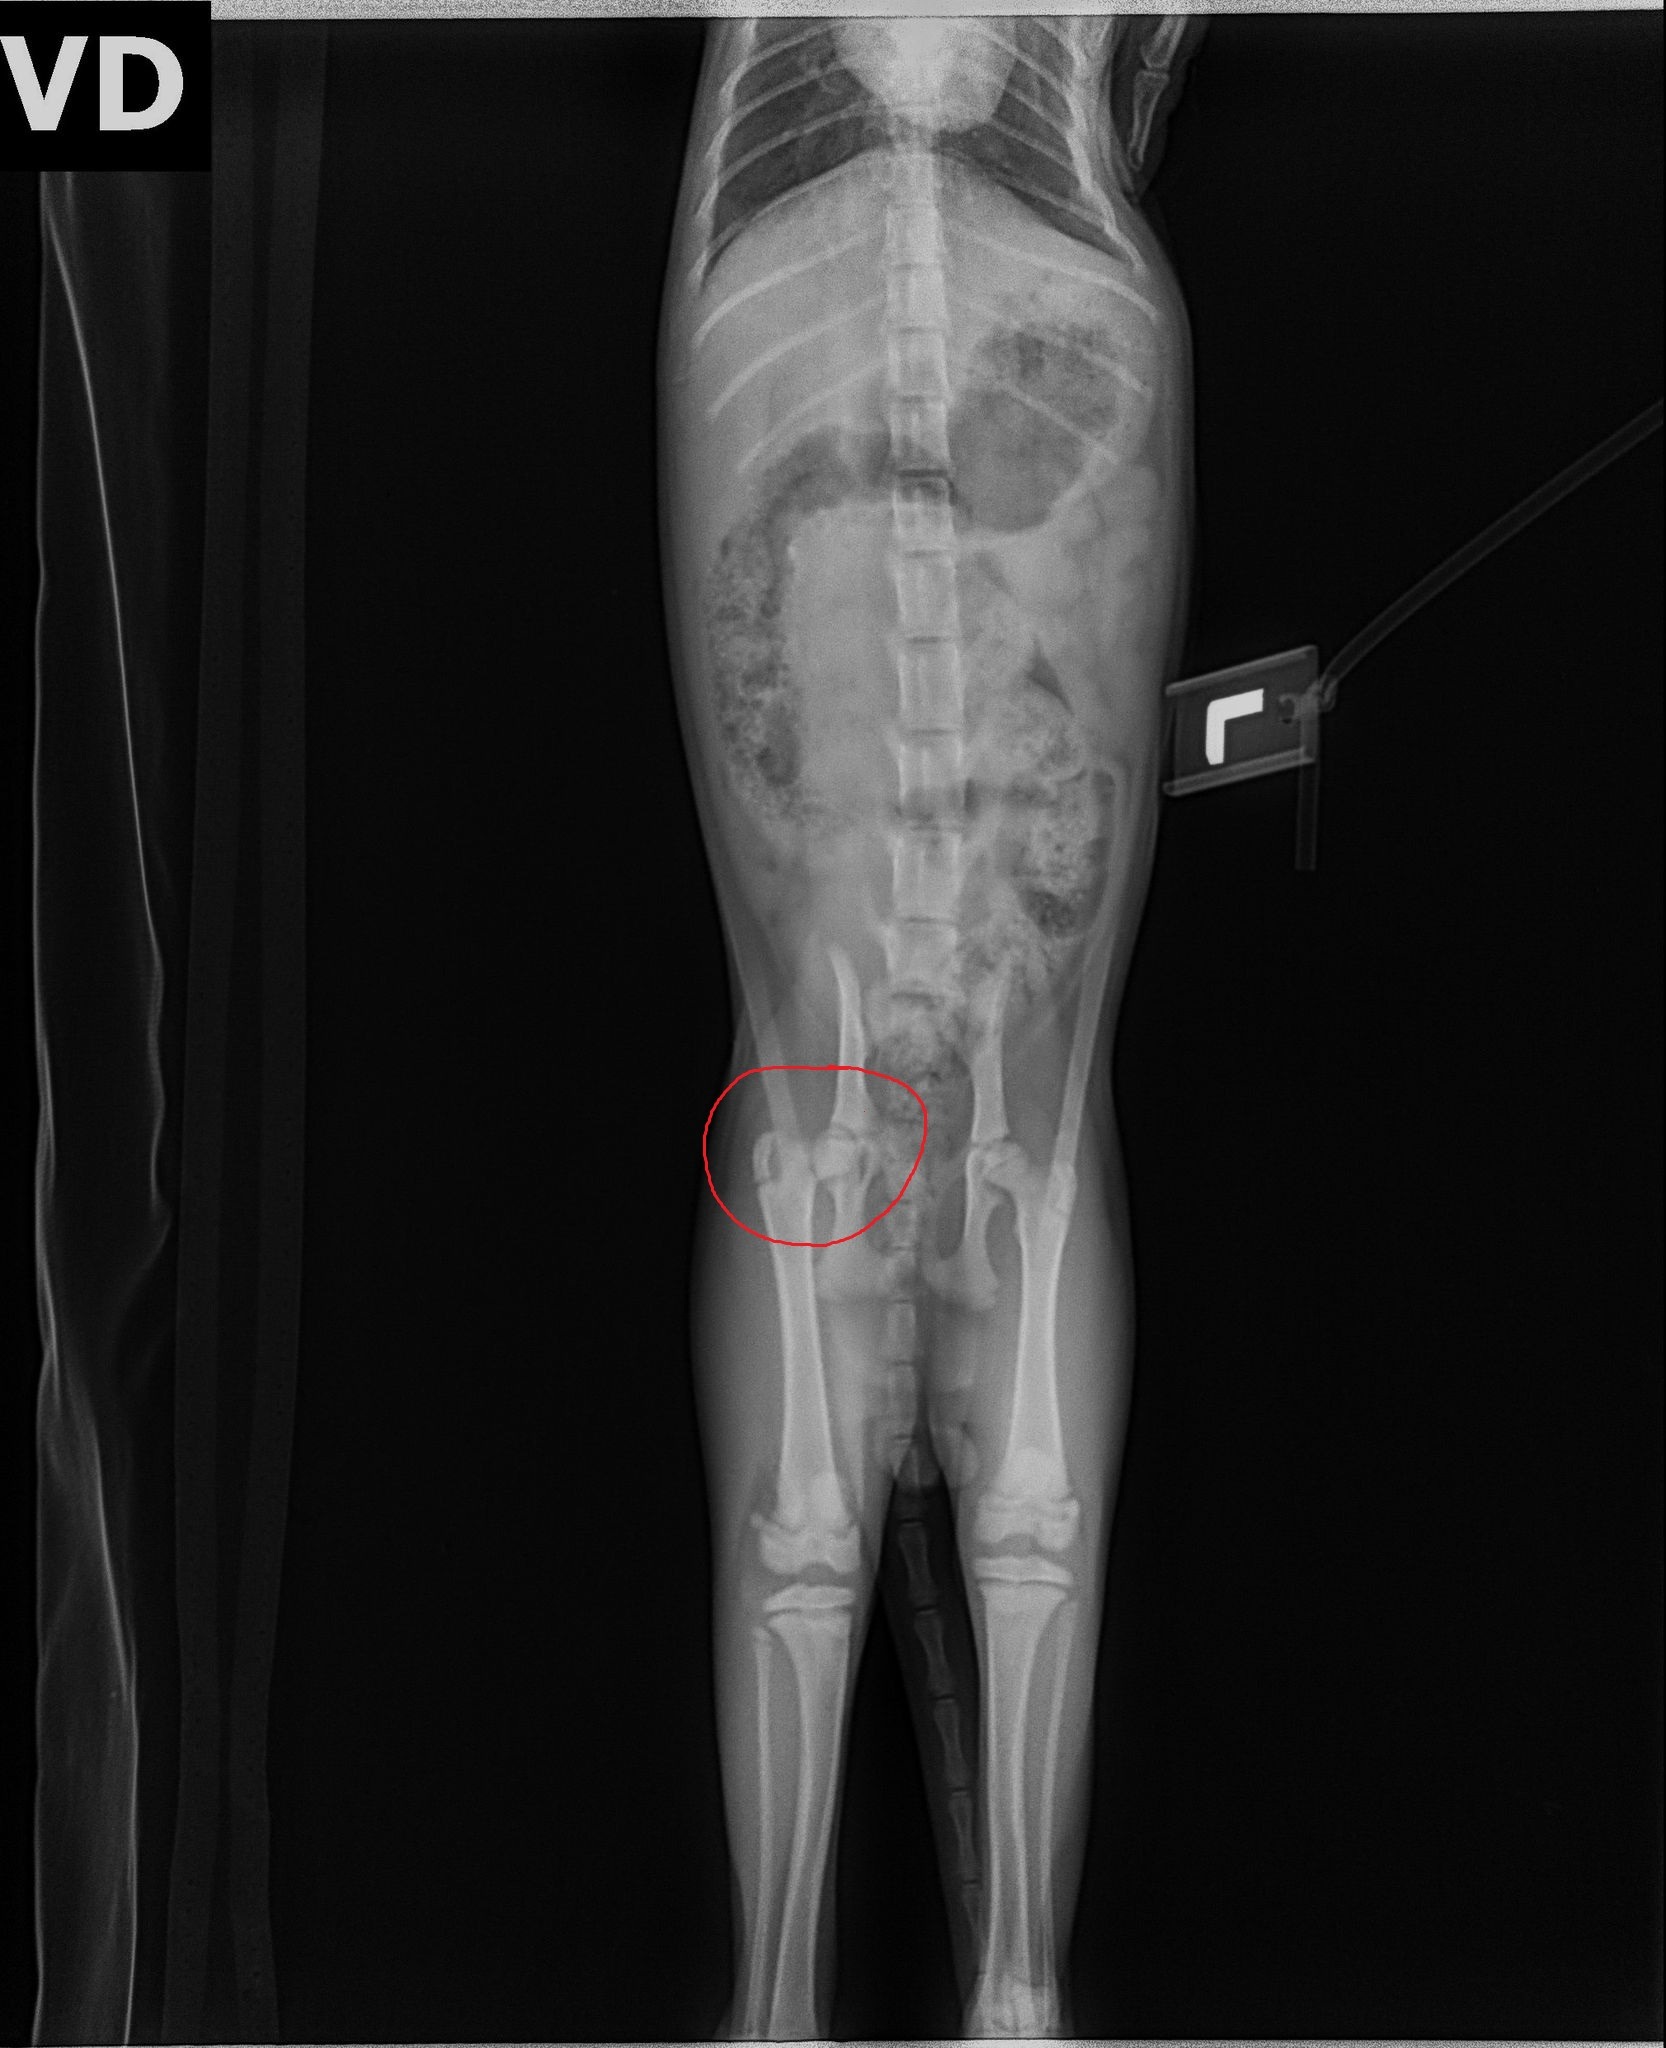

But in last month, Tiger suffered a devastating accident — he fell from a three-story building, fracturing the upper part of his right femur.

The vet has confirmed that emergency surgery is urgently needed to help Tiger walk again and prevent long-term pain or disability.

• Completed X-rays and other diagnostic tests